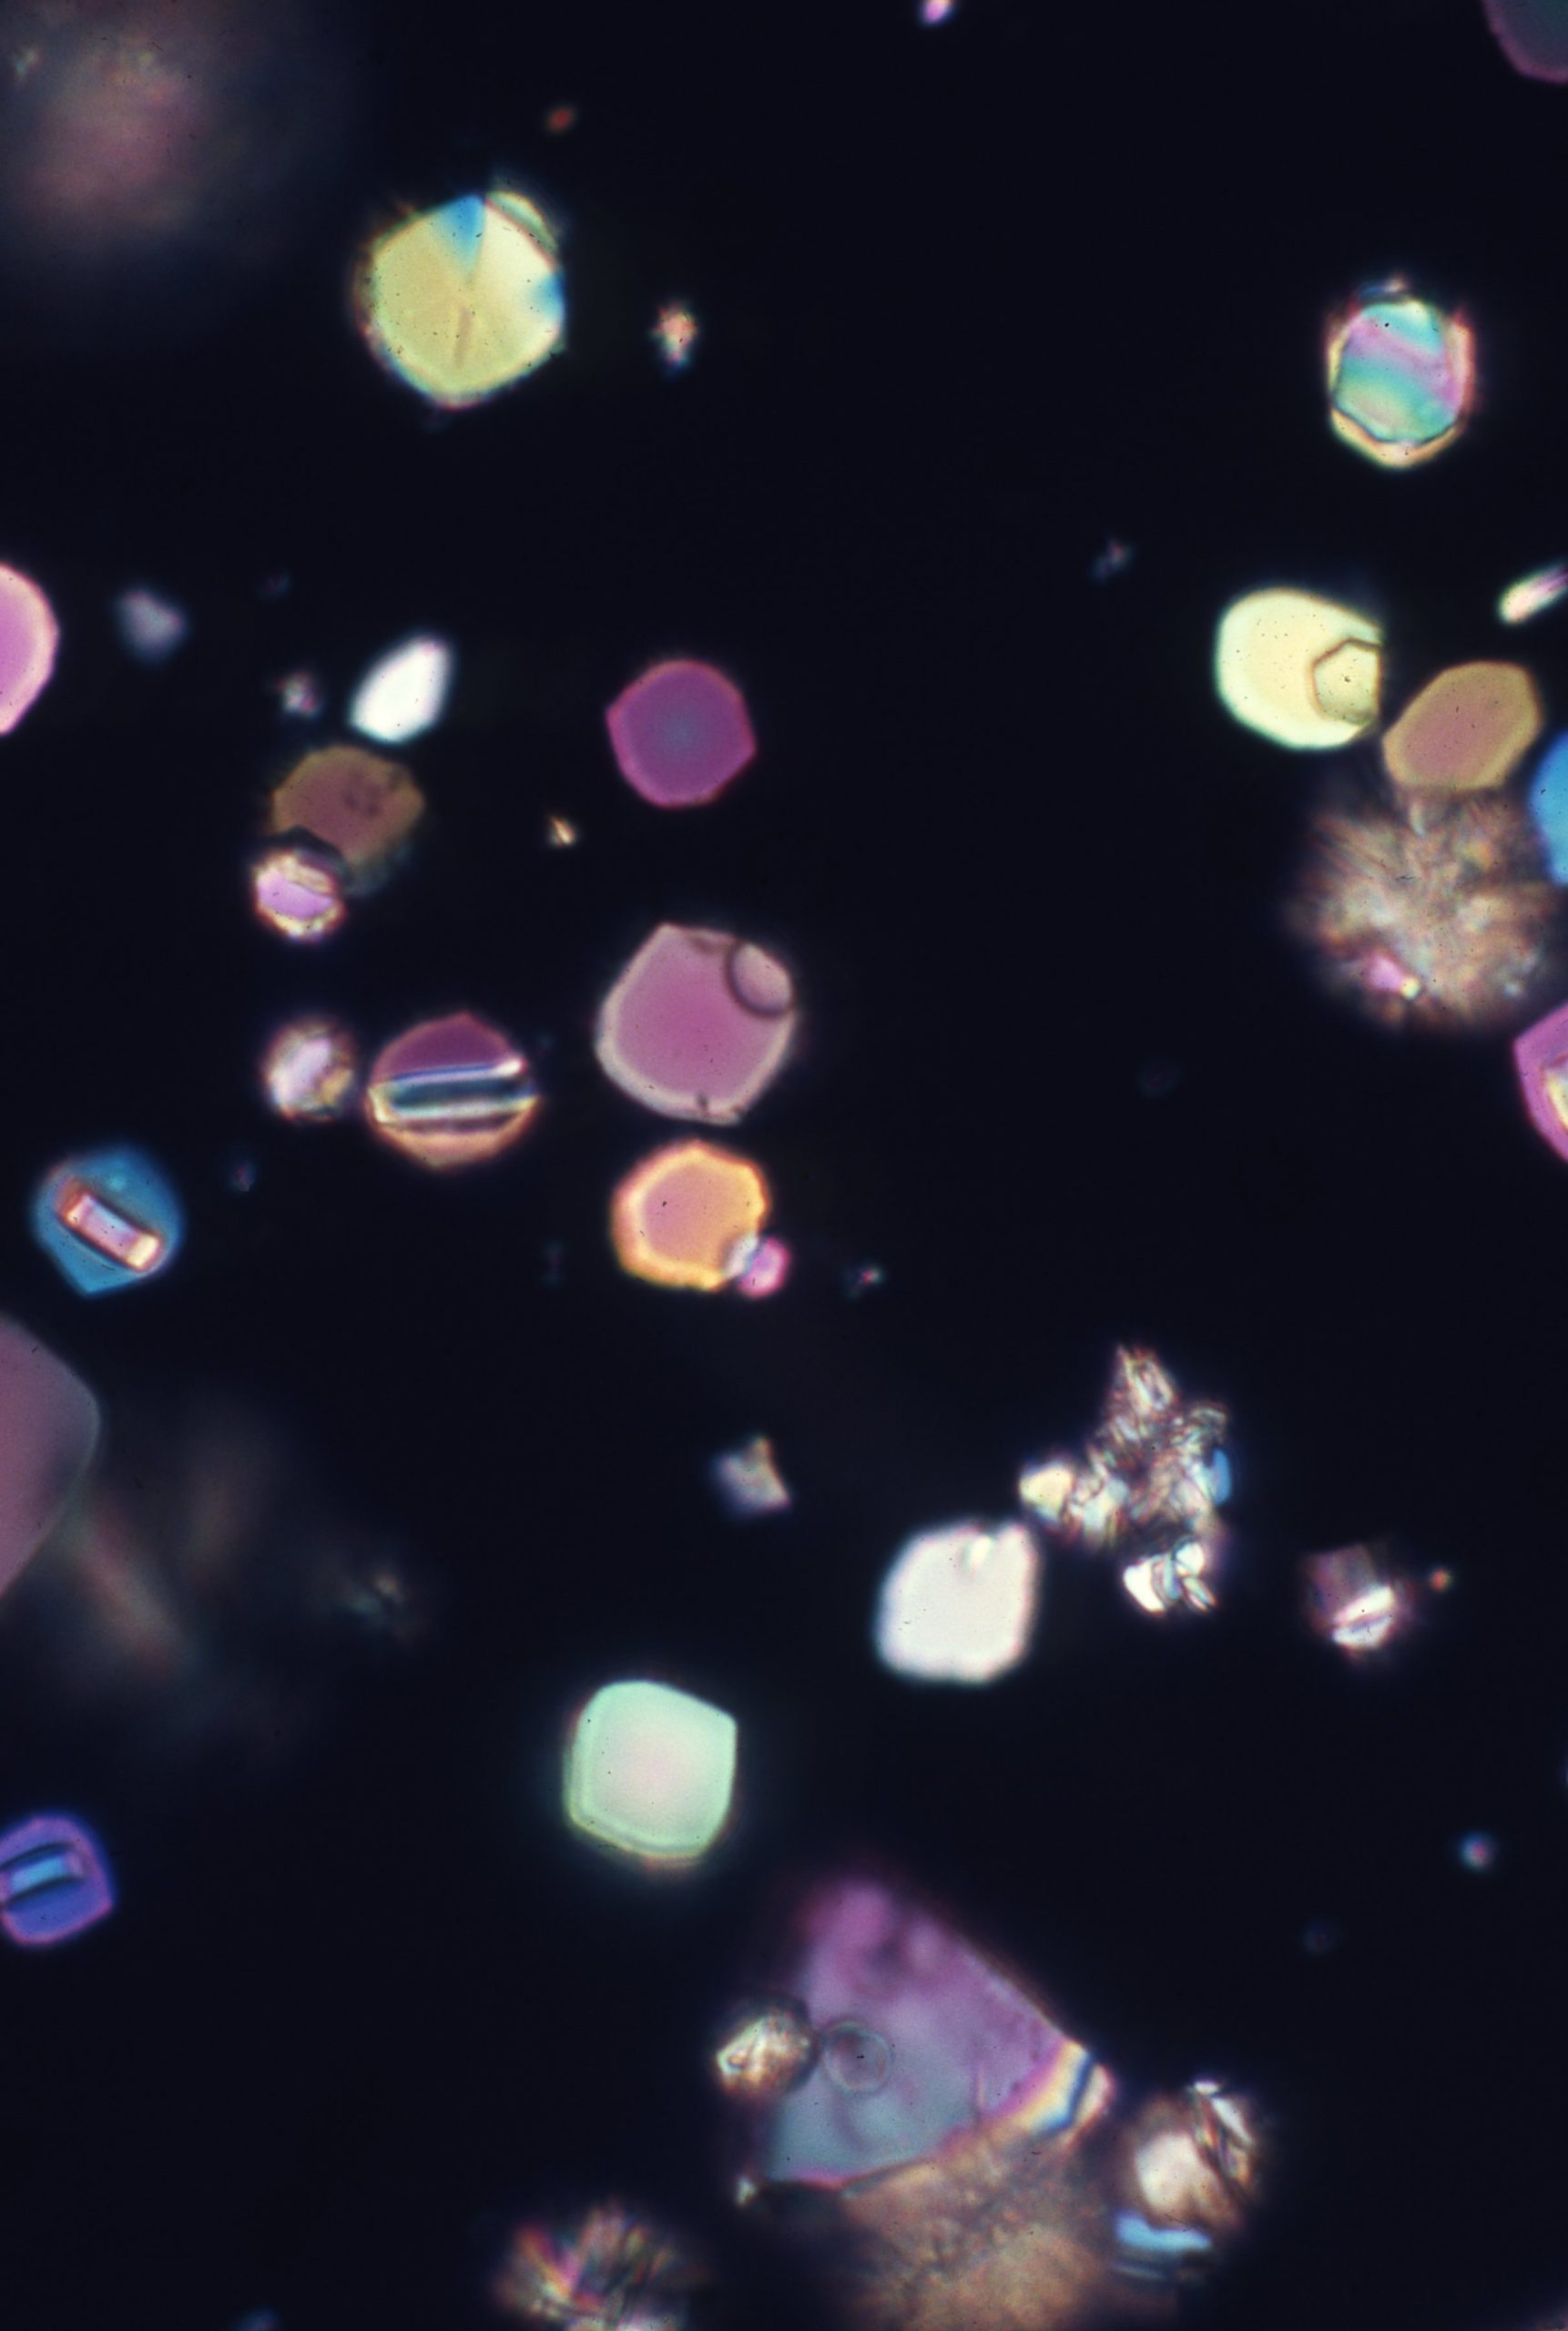

Uric acid crystals are found in acid urine, the crystal vary more in morphology than any other type of crystalThe morpholoy varies from needles, hexagonal, whestone forms, rosttes or rhombic plates Mag 10X Hexagonal forms Mag 10X Mag 10xX Mag 40X Mag 40X Mag 40X Mag 40x Mag 40X The above microphotographs are uric acid crystal with polarized light